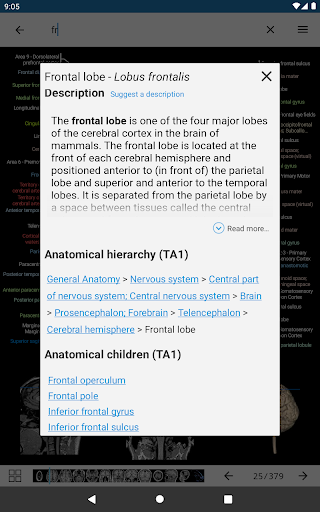

e-Anatomy tiene más de 26 000 imágenes que contienen series de imágenes en vistas axiales, coronales y sagitales, así como radiografías, angiografías, imágenes de disección, gráficos anatómicos e ilustraciones. Todas las imágenes médicas fueron etiquetadas cuidadosamente, más de 967 000 etiquetas disponibles en 12 idiomas, incluida la Terminologia Anatomica latina.

- Toque las etiquetas para mostrar las estructuras anatómicas

*Visibilidad mejorada de las definiciones de partes anatómicas

. *Navegación entre partes anatómicas usando enlaces de descripción.

la vista de detalles de una estructura anatómica ahora se muestran los términos relacionados